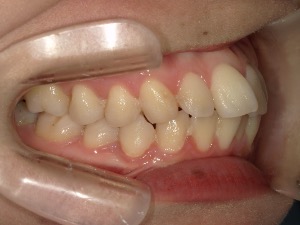

before

患者さんの年齢 20代 女性 症状 ガタガタを治したい 治療内容 マウスピース矯正治療 費用 90万(税抜) 治療期間・回数 治療期間2年、通院回数10回 メリット 笑顔が綺麗 デメリット・リスク 期間がかかることがある - マウスピース矯正